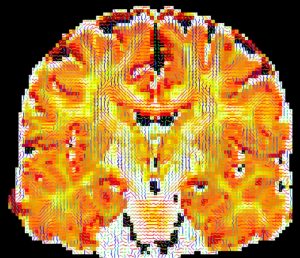

rs-fMRI

The rs-fMRI scan uses multi-band acceleration to achieve both high temporal and spatial resolution. With an eye to future data sharing, we adopted the ABCD rs-fMRI protocol, with minor adjustments. A slice acceleration factor of 6 allows a TR of 800 ms with 2.4mm iso voxels. A pair of spin-echo scans with opposite phase-encode directions provide for distortion correction. These scans are collected AC-PC -30 (adjusted as need be to fit the brain); the rotation is restricted to the x-axis, i.e. the rotation angles for the y and z axes should be set to 0. The positional parameters from the rs-fMRI should be copied to the distortion correction maps ensuring that the phase encoding directions remain correct. These three sequences should be run back-to-back with no break between scans. The acquisition time for this trio of scans is 7 minutes.